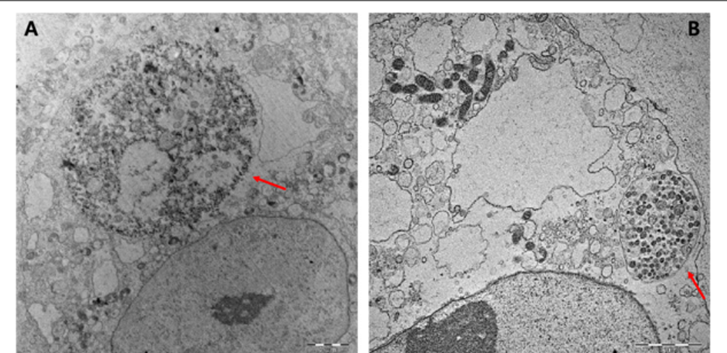

Coxiella burnetii is extremely small and difficult to visualize using routine light microscopy die to its intracellular nature and minute size. In infected host cells, the organism is typically observed within large membrane-bound vacuoles of the cytoplasm, often referred to as Coxiella-containing vacuoles. When stained with gram stain, the bacterium appears as poorly staining gram-negative coccobacilli and makes direct visualization challenging. Hence, special staining techniques such as Gimenez stain or modified Ziehl-Neelsen stain are commonly used to demonstrate the organism more clearly in infected tissues or cell cultures.

Under electron microscopy, Coxiella burnetii shows two morphological forms corresponding to its developmental cycle: the dense small cell variant and larger large cell variant within intracellular vacuoles. These microscopic characteristics reflect the bacteria’s adaptation to an intracellular lifestyle and its ability to survive in harsh intracellular environments.